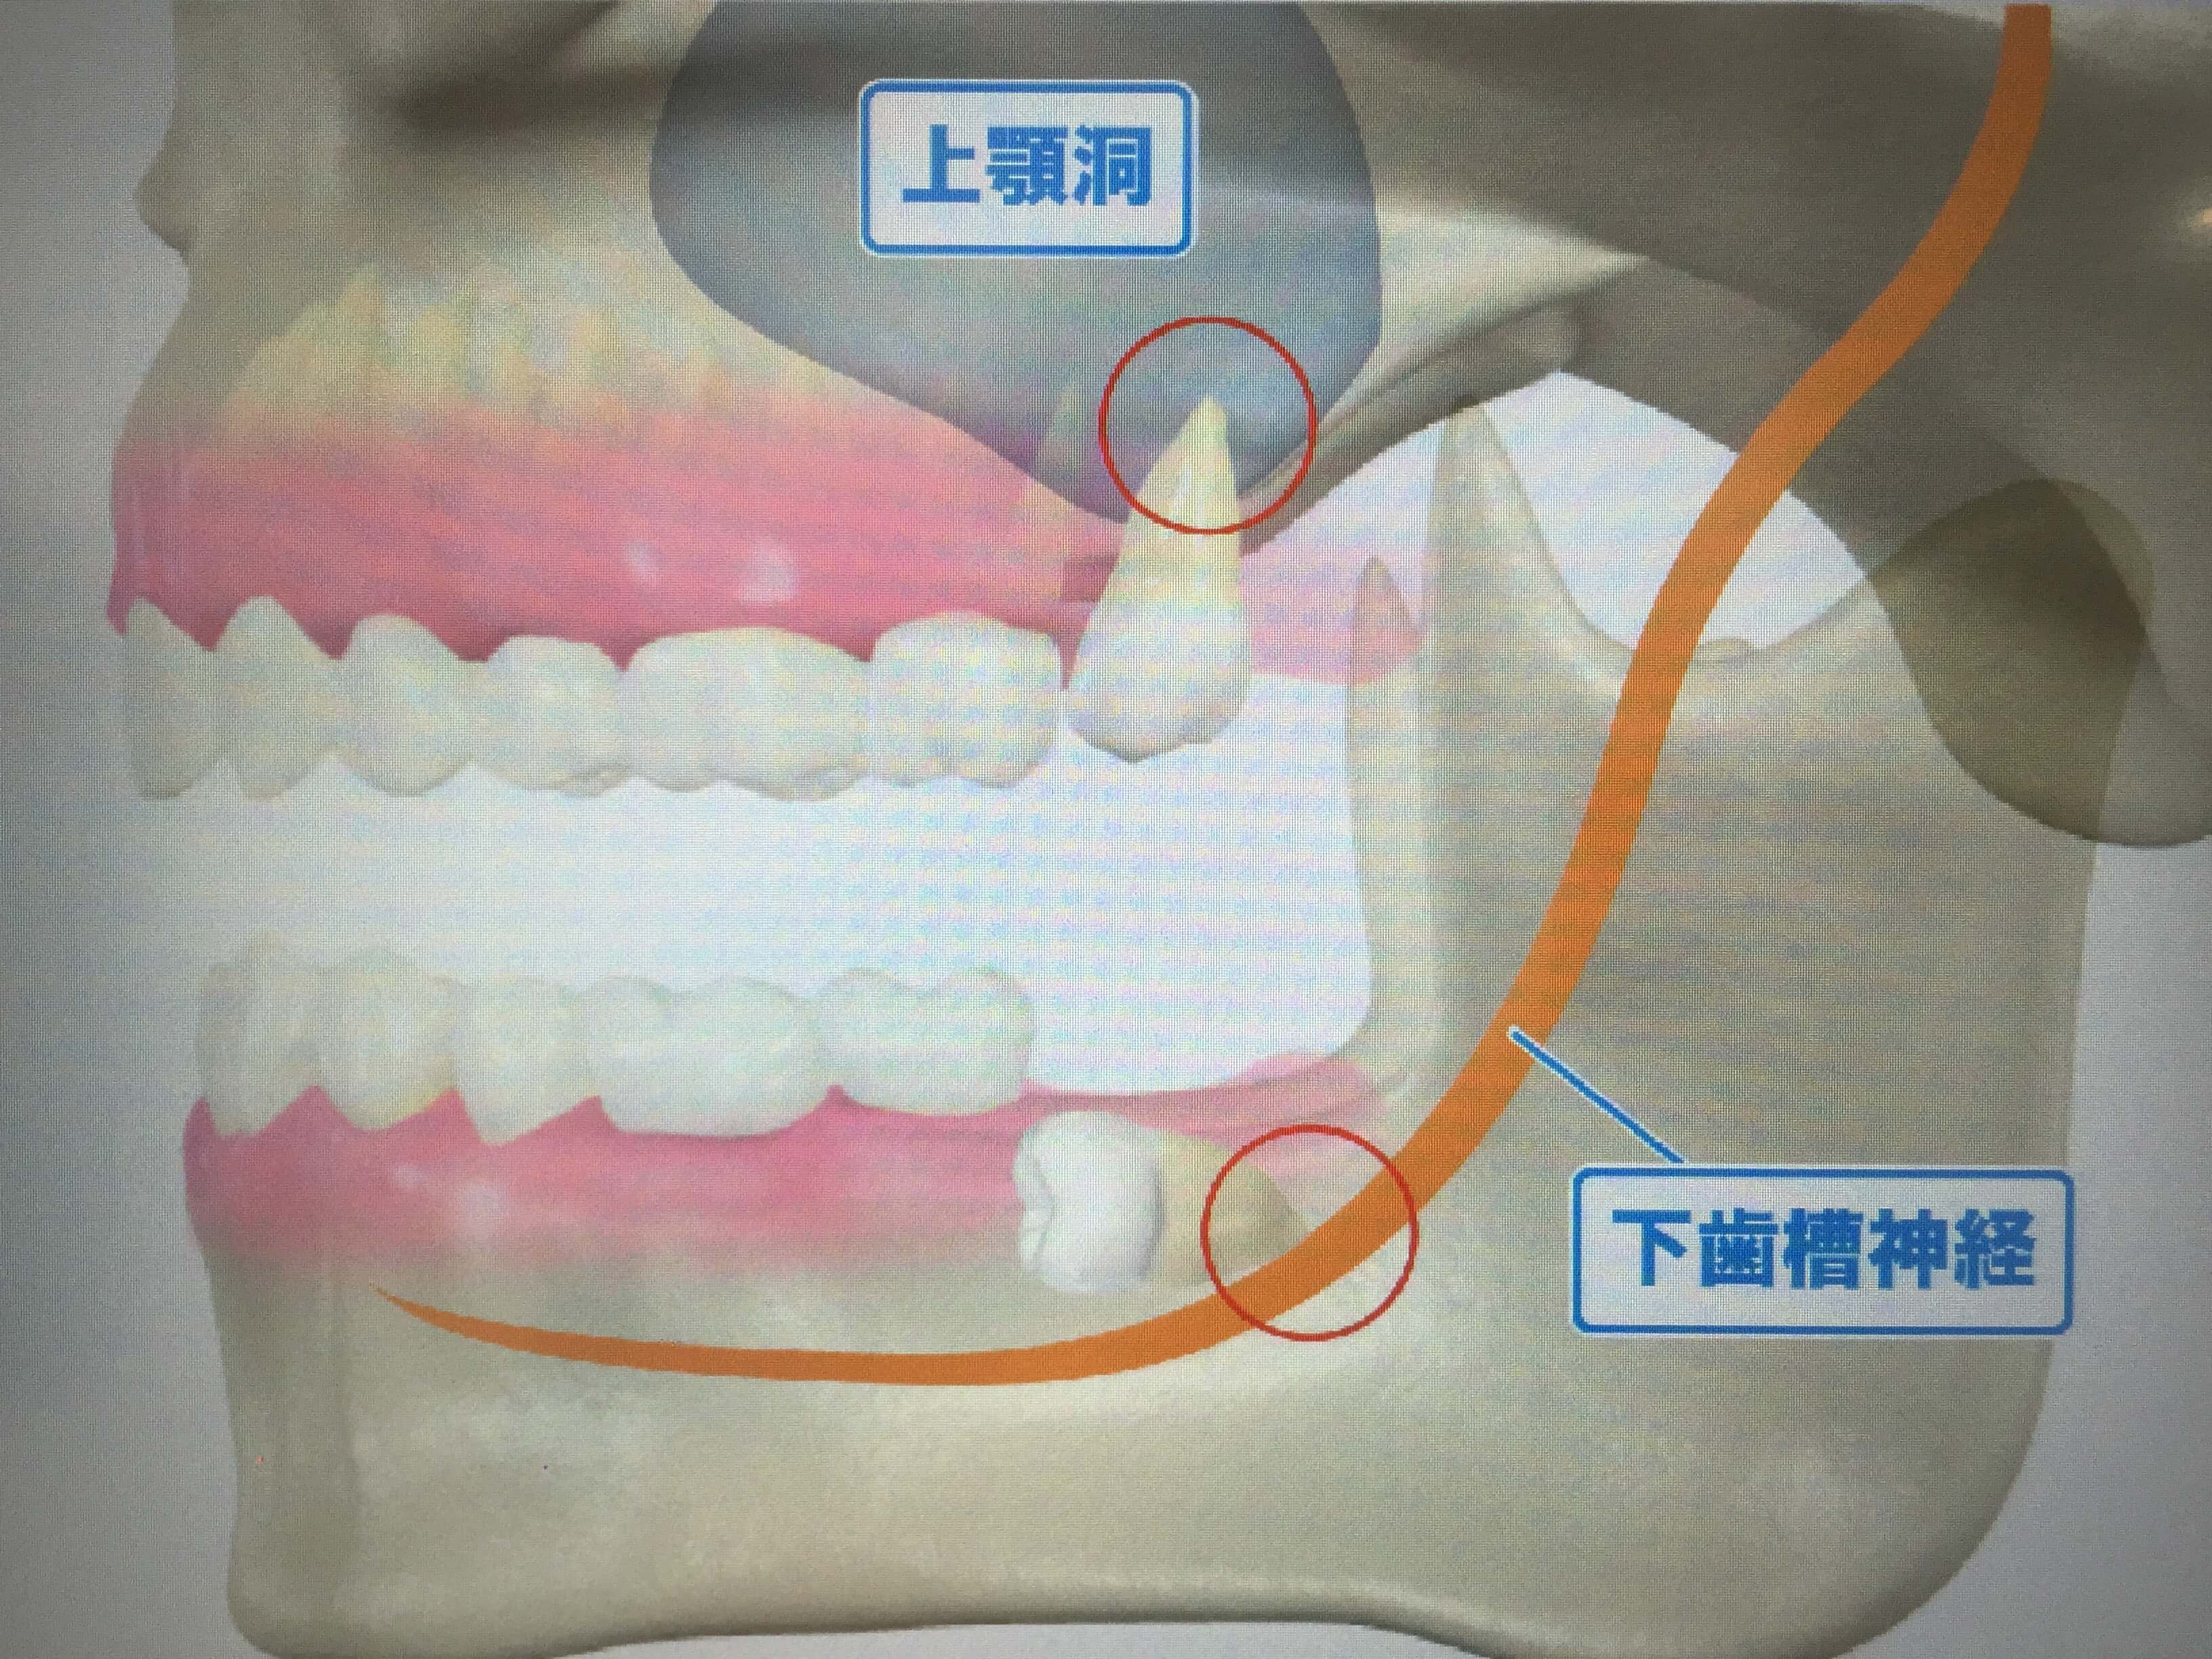

顎が小さくなっている為、親知らずの生えるスペースがなく、

斜めや真横に生える場合があり、前の歯(第2大臼歯)を圧迫し、

横から見た親知らず(ヨシダDental Cultureより)